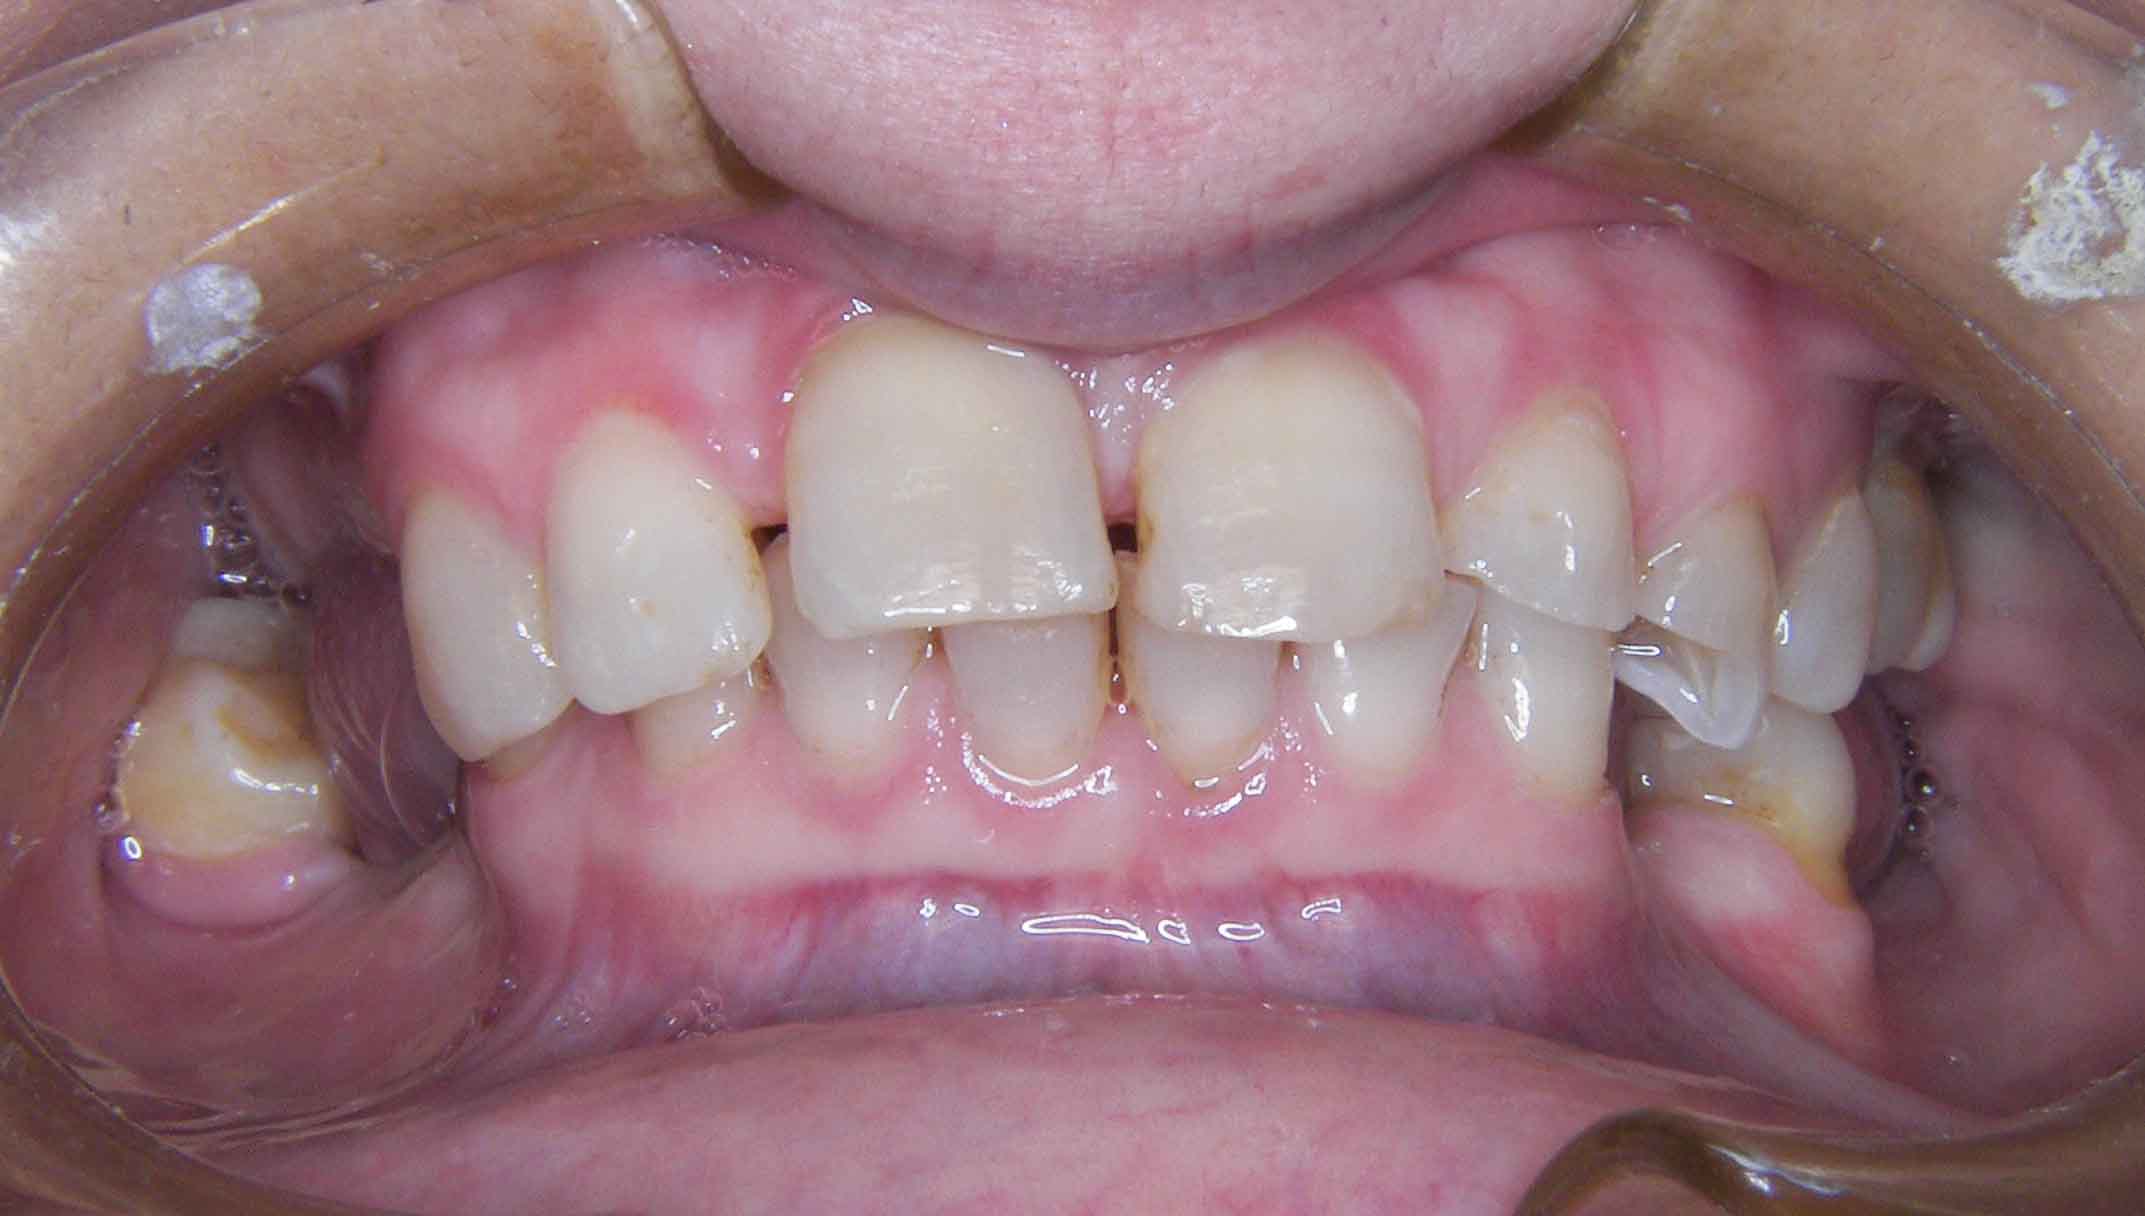

Tooth discoloration caused by tetracyclines

Aesthetic Rehabilitation with ceramic crowns and venners

Main problem:

Colour changes due to the use of tetracyclines as a child. Various treatments were done before to try to solve the problem but all of them were unsuccessful.

The Treatment:

Full crowns were opted to cover the teeth that were very damaged and venners were used to cover those who were less damaged and by doing this less natural tooth structure was damaged.